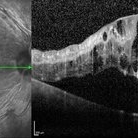

Proliferative diabetic retinopathy with fibrous proliferation over disc

SD-OCT of a 60 year old man with proliferative diabetic retinopathy post PRP laser, revealing regressed fibrous proliferation attached to the disc .